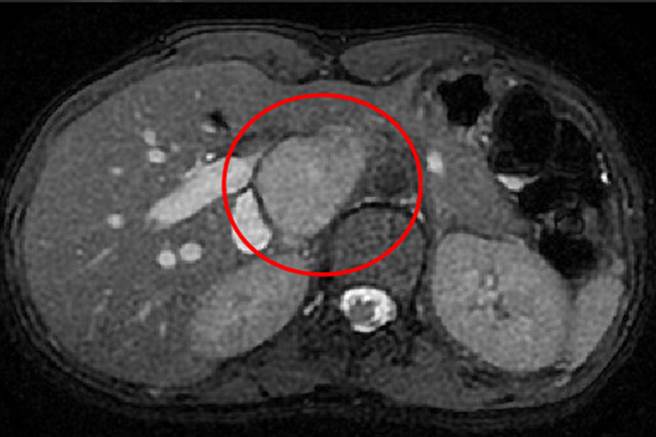

病人肝臟核磁共振檢查影像,圈起來的位置是腫瘤。(台中慈濟醫院提供/陳淑娥台中傳真)

余政展從肝臟核磁共振檢查影像確認,腫瘤位於肝臟後面、脊椎旁邊,已大到擠開腹腔多條大血管,唯一解決方式是切除病灶。但腫瘤被肝臟、胰臟與腎臟血管主動脈,還有下腔大靜脈等大血管緊緊包圍,須小心沿著大血管手術,稍一閃神幾千毫升大失血,而病人的病理報告顯示罹患「神經內分泌瘤」。